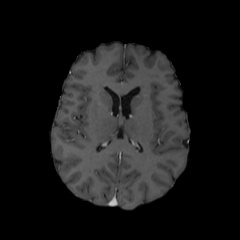

Objectives: This work aims to explore the impact of multicenter data heterogeneity on deep learning brain metastases (BM) autosegmentation performance, and assess the efficacy of an incremental transfer learning technique, namely learning without forgetting (LWF), to improve model generalizability without sharing raw data. Materials and methods: A total of six BM datasets from University Hospital Erlangen (UKER), University Hospital Zurich (USZ), Stanford, UCSF, NYU and BraTS Challenge 2023 on BM segmentation were used for this evaluation. First, the multicenter performance of a convolutional neural network (DeepMedic) for BM autosegmentation was established for exclusive single-center training and for training on pooled data, respectively. Subsequently bilateral collaboration was evaluated, where a UKER pretrained model is shared to another center for further training using transfer learning (TL) either with or without LWF. Results: For single-center training, average F1 scores of BM detection range from 0.625 (NYU) to 0.876 (UKER) on respective single-center test data. Mixed multicenter training notably improves F1 scores at Stanford and NYU, with negligible improvement at other centers. When the UKER pretrained model is applied to USZ, LWF achieves a higher average F1 score (0.839) than naive TL (0.570) and single-center training (0.688) on combined UKER and USZ test data. Naive TL improves sensitivity and contouring accuracy, but compromises precision. Conversely, LWF demonstrates commendable sensitivity, precision and contouring accuracy. When applied to Stanford, similar performance was observed. Conclusion: Data heterogeneity results in varying performance in BM autosegmentation, posing challenges to model generalizability. LWF is a promising approach to peer-to-peer privacy-preserving model training.